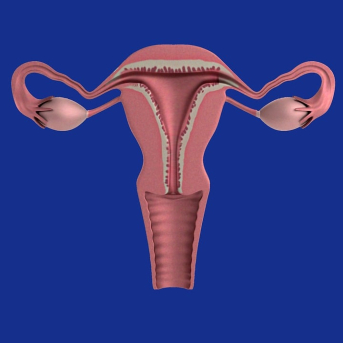

Os médicos aconselham a utilização dos remédios para engravidar em mulheres que tem ovulação irregular ou que tem ausência total da ovulação. Obviamente após investigação do casal, no caso da mulher com ultrassonografias para verificação de obstrução de trompas e o homem espermograma para verificação da qualidade do sêmen.

O foco dos remédios são melhorar a qualidade e quantidade dos óvulos, sendo um processo cuidadoso e ponderado pelo especialista, pois ao obter muitos óvulos é arriscada a gestação de múltiplos, gêmeos, trigêmeos etc. A indicação dos remédios para engravidar também ocorre para casais que são tentantes há um período superior a um ano e não conseguiram a gestação de forma natural.

Para Mulheres: Anatômicos, imunológicos e casos de endometriose. Alterações hormonais, amenorreia (períodos sem menstruação), falta de ovulação ou ovulação de ovócitos imaturos ou com má formação.